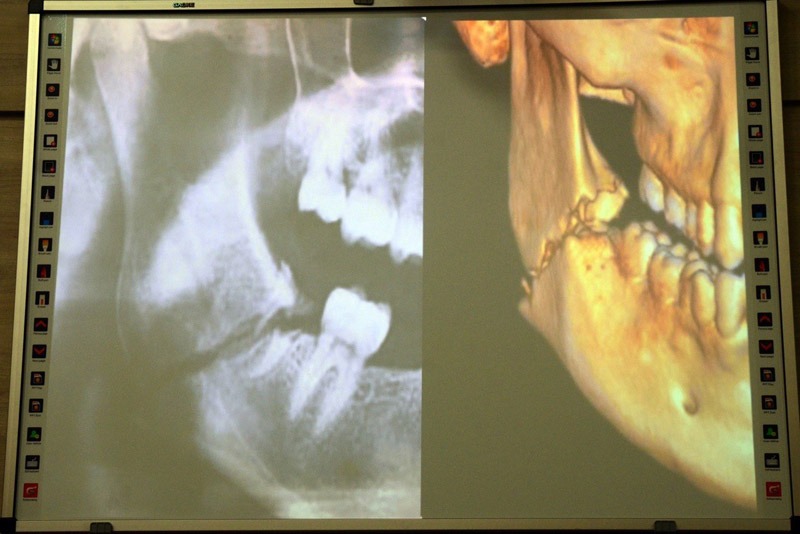

Під час лекції учасники розглянули практичні аспекти збереження кісткової тканини, алгоритми підбору імплантатів для різних клінічних випадків, а також типові помилки, які можуть вплинути на довгостроковий результат лікування.